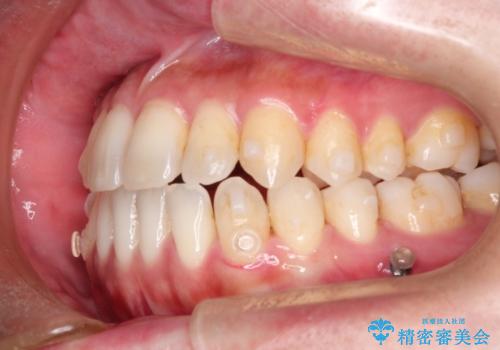

Invisalign インビザライン によるガタつき、受け口傾向の改善

- 拡大・IPRによるスペースゲインを主とした非抜歯・マウスピース矯正を計画しました。

奥歯の位置関係の修正は難儀することが多いマウスピース矯正ですが、割とスムーズに奥歯の位置関係の修正をすることができました。

クロスバイトもきれいになり、きれいな歯並びとなりました。